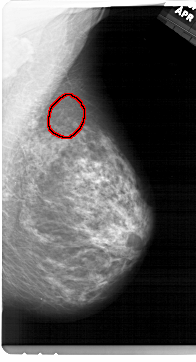

A_1315_1.RIGHT_MLO

RIGHT_MLO LINES 6871 PIXELS_PER_LINE 3706 BITS_PER_PIXEL 12 RESOLUTION 43.5 OVERLAY

FILE: A_1315_1.RIGHT_MLO.OVERLAY

TOTAL_ABNORMALITIES 1

ABNORMALITY 1

LESION_TYPE CALCIFICATION TYPE PLEOMORPHIC DISTRIBUTION CLUSTERED

ASSESSMENT 4

SUBTLETY 2

PATHOLOGY BENIGN

TOTAL_OUTLINES 1

BOUNDARY